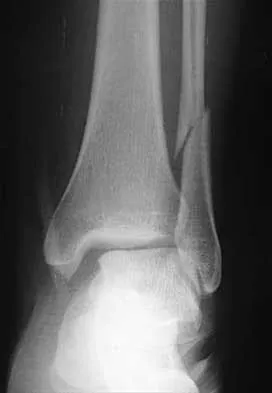

A 25-year-old woman has significant pain and swelling in her left ankle after falling off her bicycle. Examination reveals that she is neurovascularly intact. Radiographs are shown in Figures 33a through 33c. What is the next most appropriate step in management?

Explanation